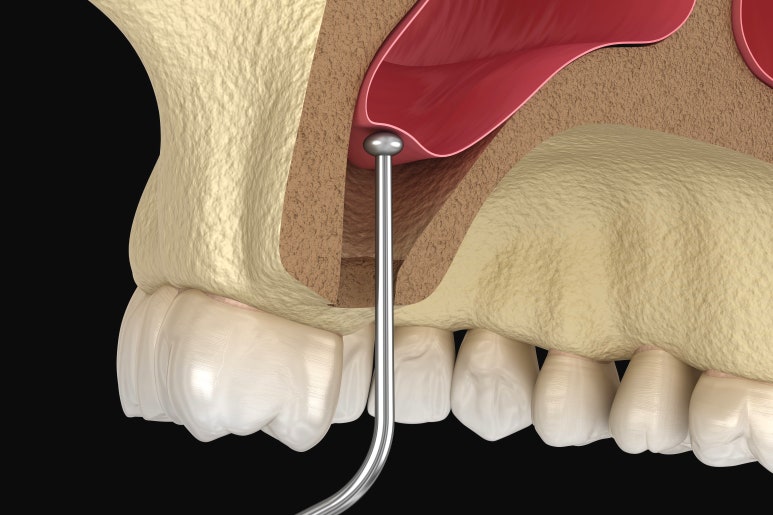

상악동 거상술은 크게 2가지가 있습니다.

인공치아를 심으려는 위치에 드릴로 구멍을 내서 구멍에 바로 뼈이식을 하는 1)크레스탈 어프로치가 있고요.

옆에서 구멍을 뚫고 들어가서 뼈이식을 하는 2)라테랄 어프로치가 있습니다.

만일 뼈이식 양이 많지 않고 이식해야 할 부위에 이상한 구조물도 없는 경우라면 크레스탈 어프로치로 진행되고요.

이와 반대로 뼈이식을 많이 해야 하거나, 이상한 구조물이 있다면 이때는 라테랄 어프로치로 진행해야 합니다.

더군다나 크레스탈 어프로치는 상악동 막을 직접 보고 시술하는 것이 아니라,

감각으로 하는 것이기 때문에 많이 올리려고 무리해서 진행하다 보면 자칫 막이 찢어질 수도 있습니다.

따라서 뼈이식을 많이 해야 할 때는 라테랄 어프로치, 즉 옆으로 들어가서 직접 막을 눈으로 보면서 수술하는 것을 고려하게 됩니다.